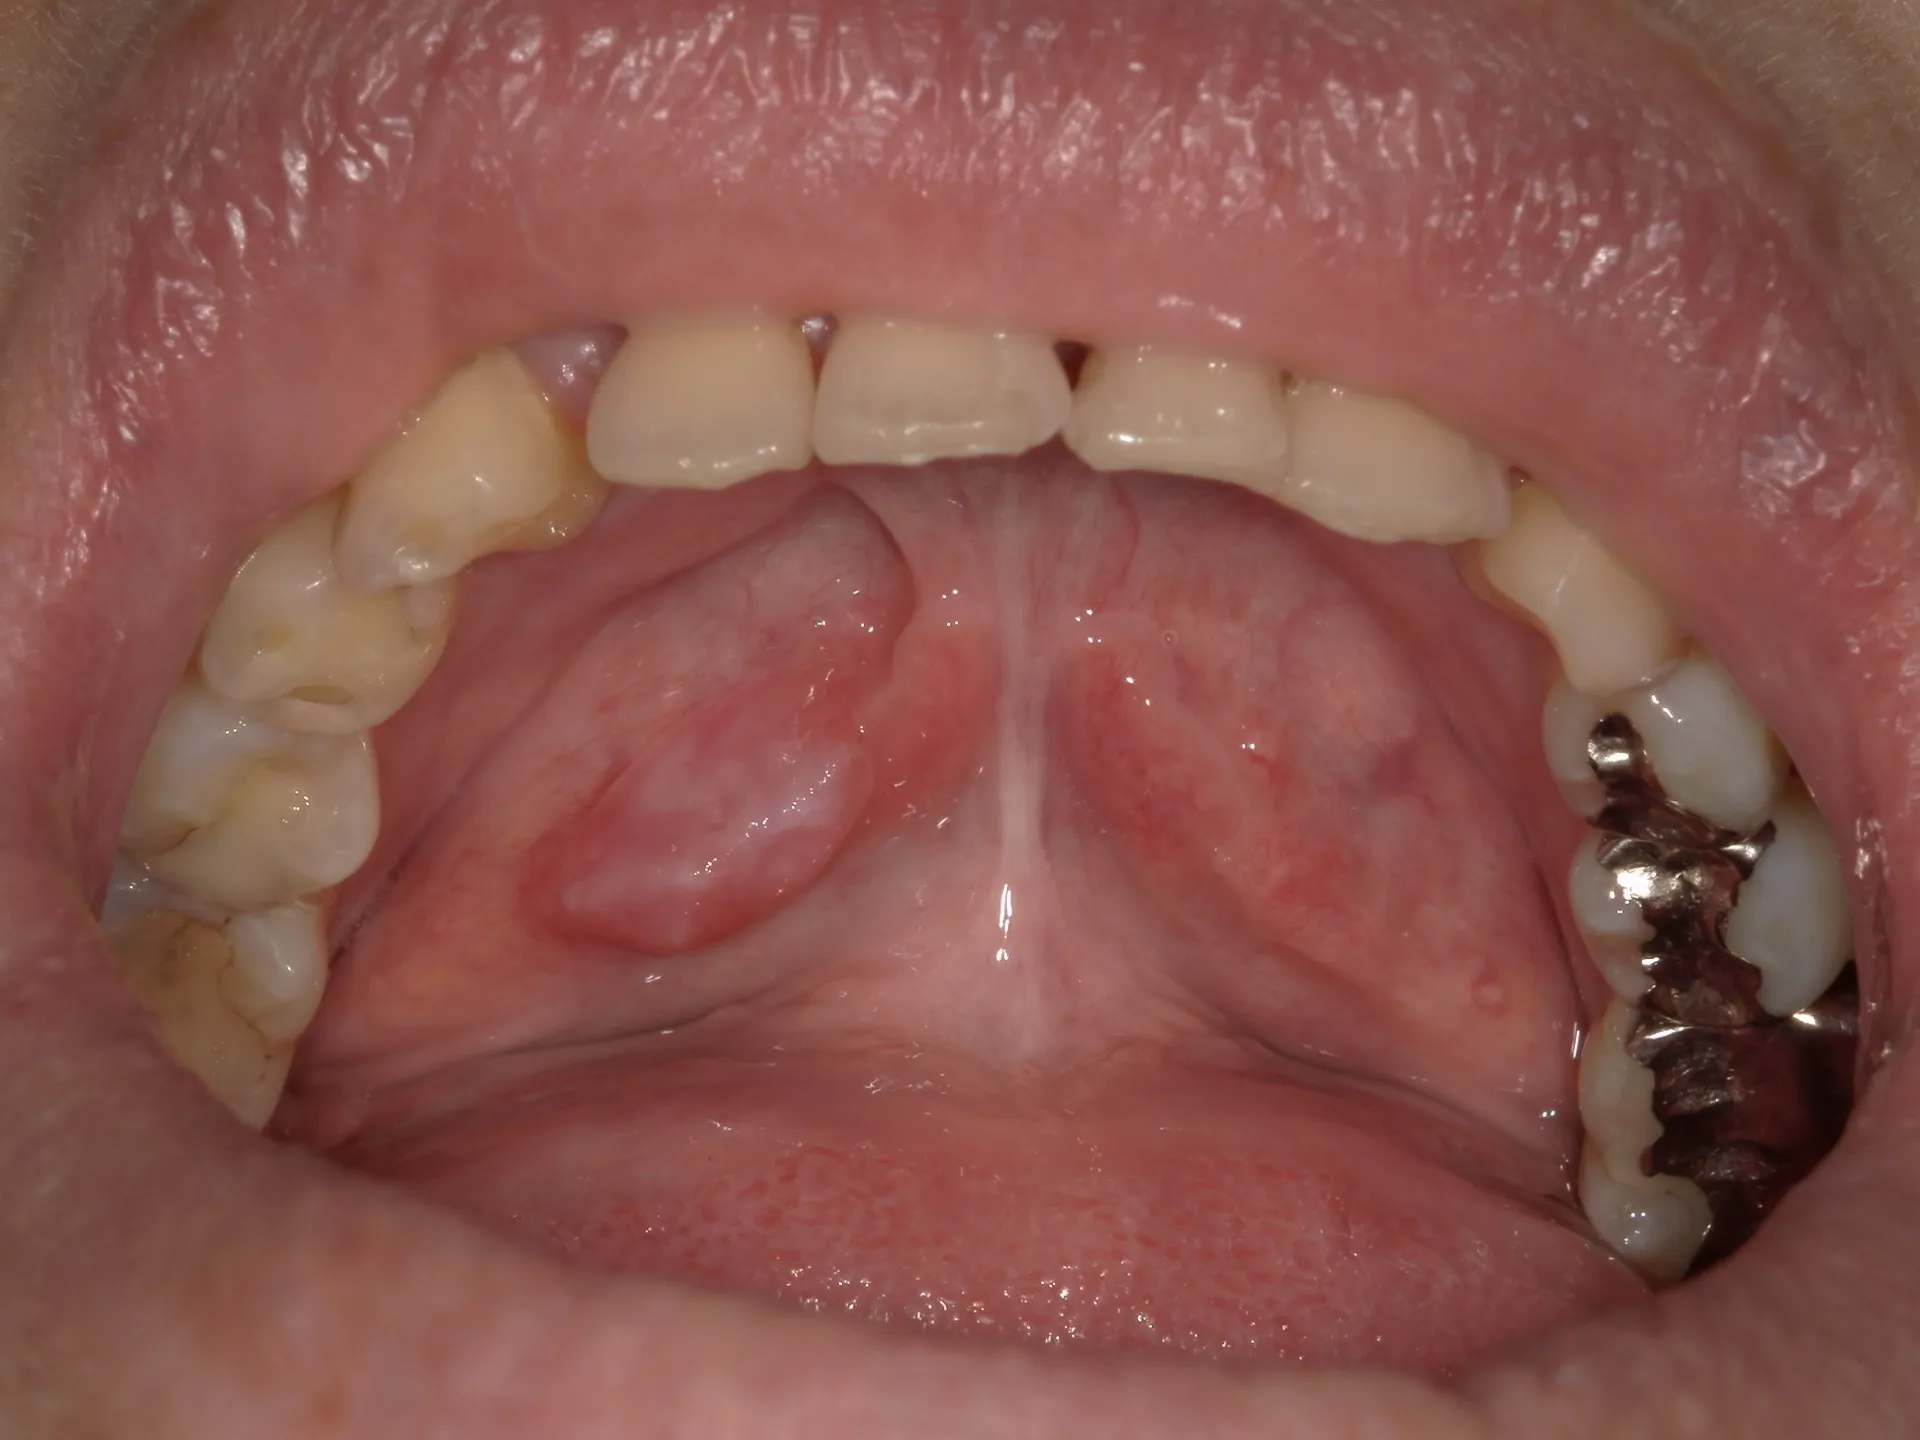

舌の下に膨らんだ出来物

舌の下(口腔底)に膨らみができたことはありませんか?

今回の病態はガマ腫とよばれ、

唾液の工場から外に排出されるべき管が何かの拍子に破れて、組織の中に溢れ出た状態が膨らんでいるのです。

・痛みはほぼなく柔らかいドーム状をしている。

・腫脹のスピードは緩やか。

・内部はやや透明感のある青。